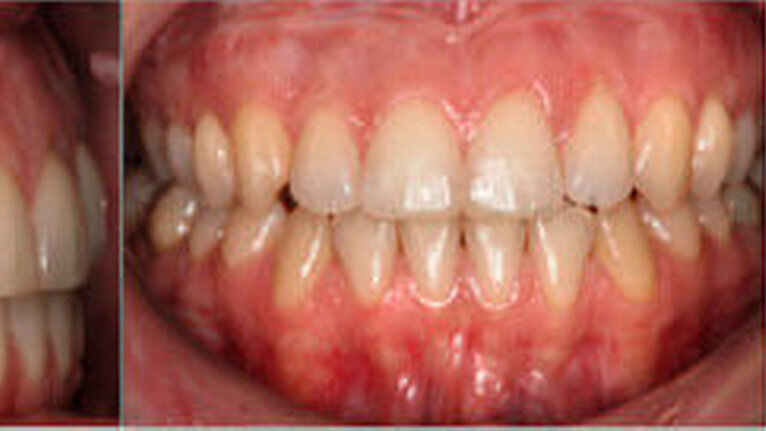

Die postoperative kieferorthopädische Aufgabe bestand in der okklusalen Feineinstellung, die mittels 0.18.2 x 0.18.2 TMA- Bogen und dem vertikalen, triangulären Einhängen von Klasse-IV-Elastics realisiert wurde. Die Patientin befand sich zusätzlich in logopädischer und in physiotherapeutischer Behandlung. Das Debonding der lingualen Apparatur erfolgte etwa fünf Monate nach der Operation (Abbildung 7).

Die aktuelle Dokumentation befindet sich eineinhalb Jahre nach Behandlungsabschluss (Abbildung 8). Die Patientin wird weiterhin jährlich kontrolliert, die Befunde werden dokumentiert und sie weist zurzeit kein Rezidiv auf. Sie ist hinsichtlich des Therapieverlaufs und des Behandlungsergebnisses sehr zufrieden.